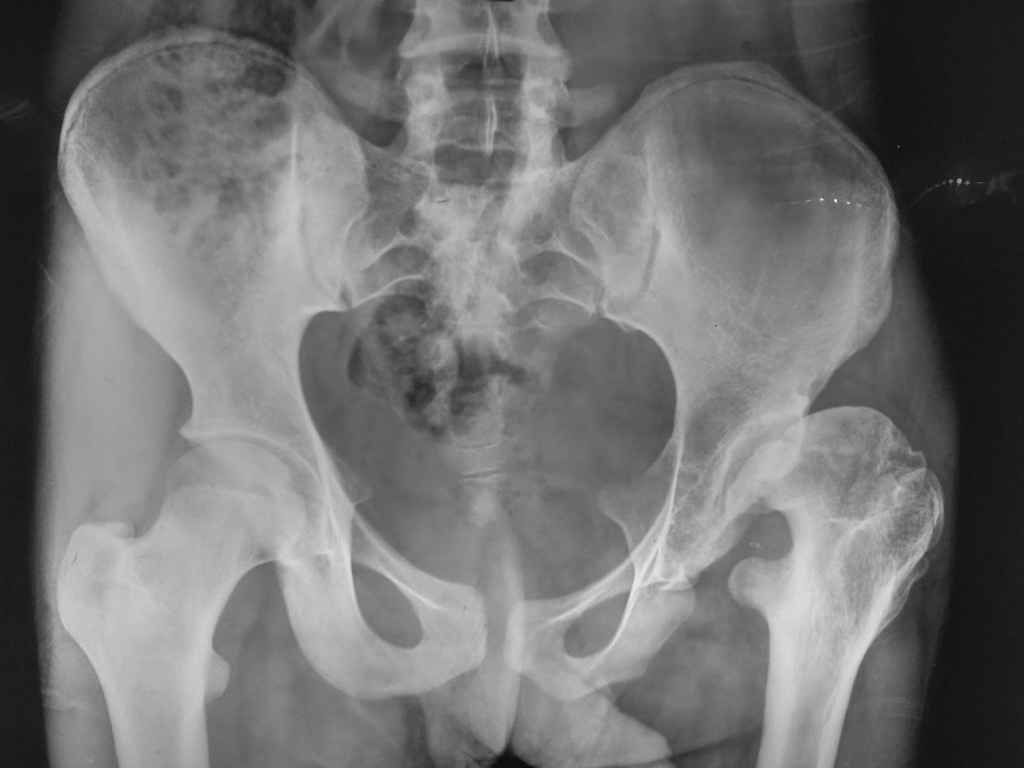

Patients Age 17 years.LLD 3 inches,

Unable to squat and sit cross leg.Flexion at hip 90 deg, abduction adduction 5-10 degree.

evolution of this hip is to a degenerative arthritis. I suggest periacetabular osteotomy to provide coverage of femoral head, associated to varus and derotative proximal femural osteotomy (femural neck seems valgus and antiverse). This can slow degenerative progression. Dysmetria is not so important as pain. If you neglect this hip, it should become painful and arthritic.

I think this is "lost case" not situable for any reconstructive osteotomy(like mentioned above PAO).This girl already had pseudoaceetabulum and degenerative arthritis.Two practic solutions: THR(later) or pelvic support osteotomy( if you know how to do it).